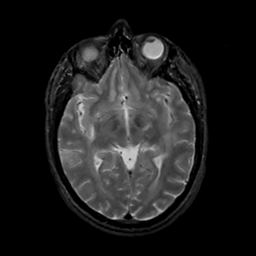

MR Study #13, May 19, 1991 -- Slice #23